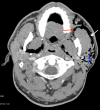

Pneumoparotid refers to the presence of air within the parotid gland and pneumoparotitis indicates overlying inflammation or infection. Several physiologic mechanisms exist to prevent the reflux of air and oral contents into the parotid gland, however, these safeguards can be overcome by high intraoral pressures, thus provoking pneumoparotid. Whereas the relationship between pneumomediastinum and air dissecting up into cervical tissues is well understood, the relationship between pneumoparotitis and free air traveling downwards through contiguous structures within the mediastinum is less defined. We present a case of a gentleman who experienced the sudden onset of facial swelling and crepitus in the context of inflating an air mattress with his mouth, who was ultimately found to have pneumoparotid with consequent pneumomediastinum. Discussion of this unusual presentation is important to facilitate recognition and treatment of this uncommon pathology.